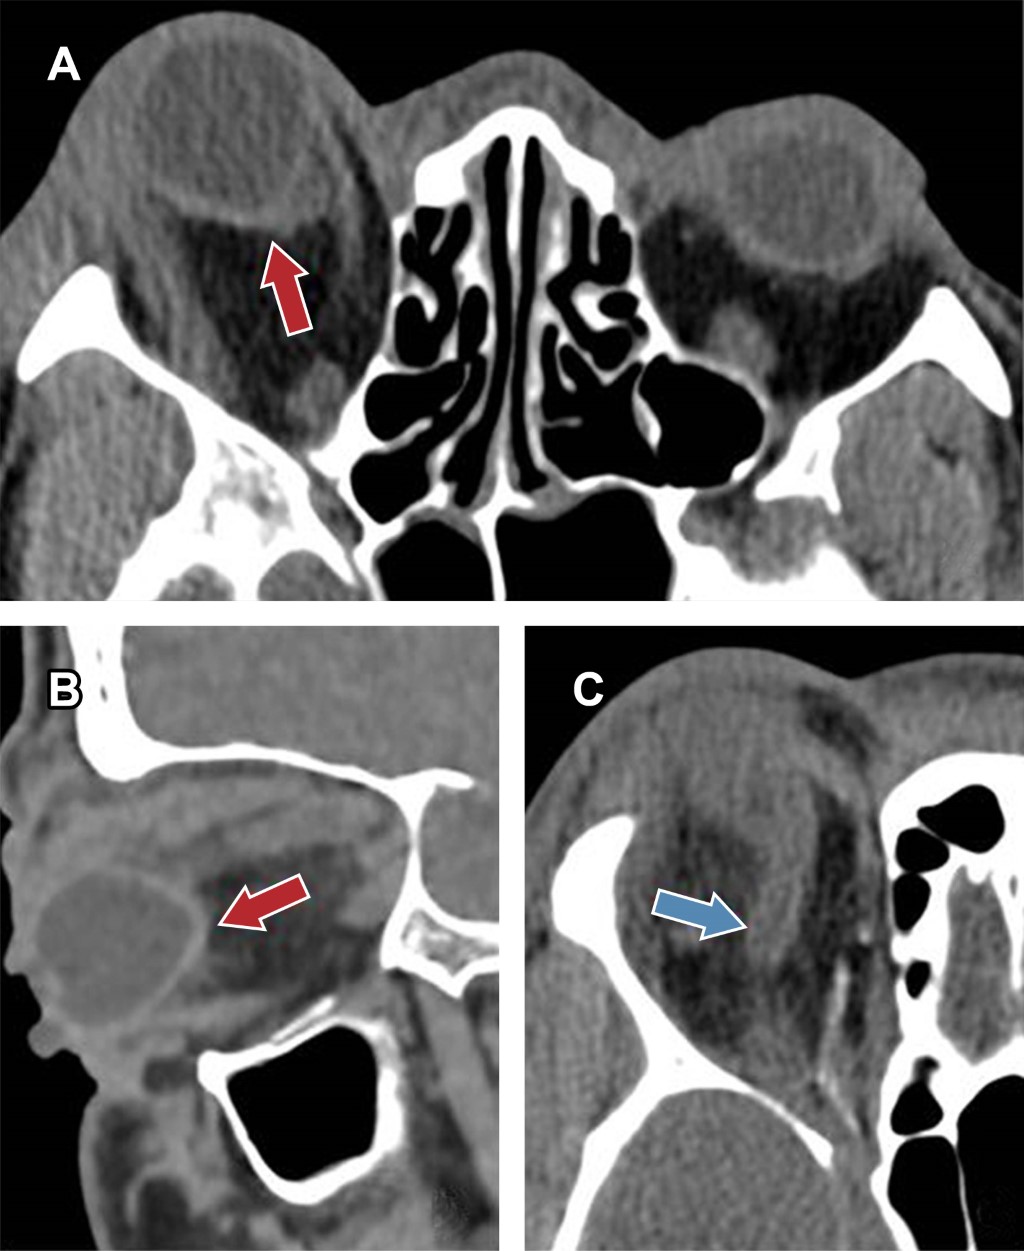

Se le realizó una tomografía computarizada (TC) que mostró una vena oftálmica superior derecha aumentada de tamaño, con hiperdensidad en su interior, sugestiva de trombosis (Figura 2C). También presentaba trabeculación de la grasa postseptal de la órbita derecha con importante proptosis asociada del globo ocular y celulitis orbitaria. Por último, se objetivó tanto en el plano axial como en el sagital el signo del "tenting posterior" del globo ocular derecho (Figura 2A y B), siendo los hallazgos en conjunto indicativos de un síndrome compartimental orbitario.

Figura 2